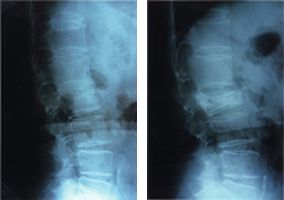

骨粗鬆症の強い高齢の女性が、転倒など軽微な外力でも受傷してしまう場合(図1)と、若年者が、交通事故や労災事故で、転落するなど強大な外力で受傷する場合とに、大きく2分されます。

脊椎圧迫骨折_01

(図1)